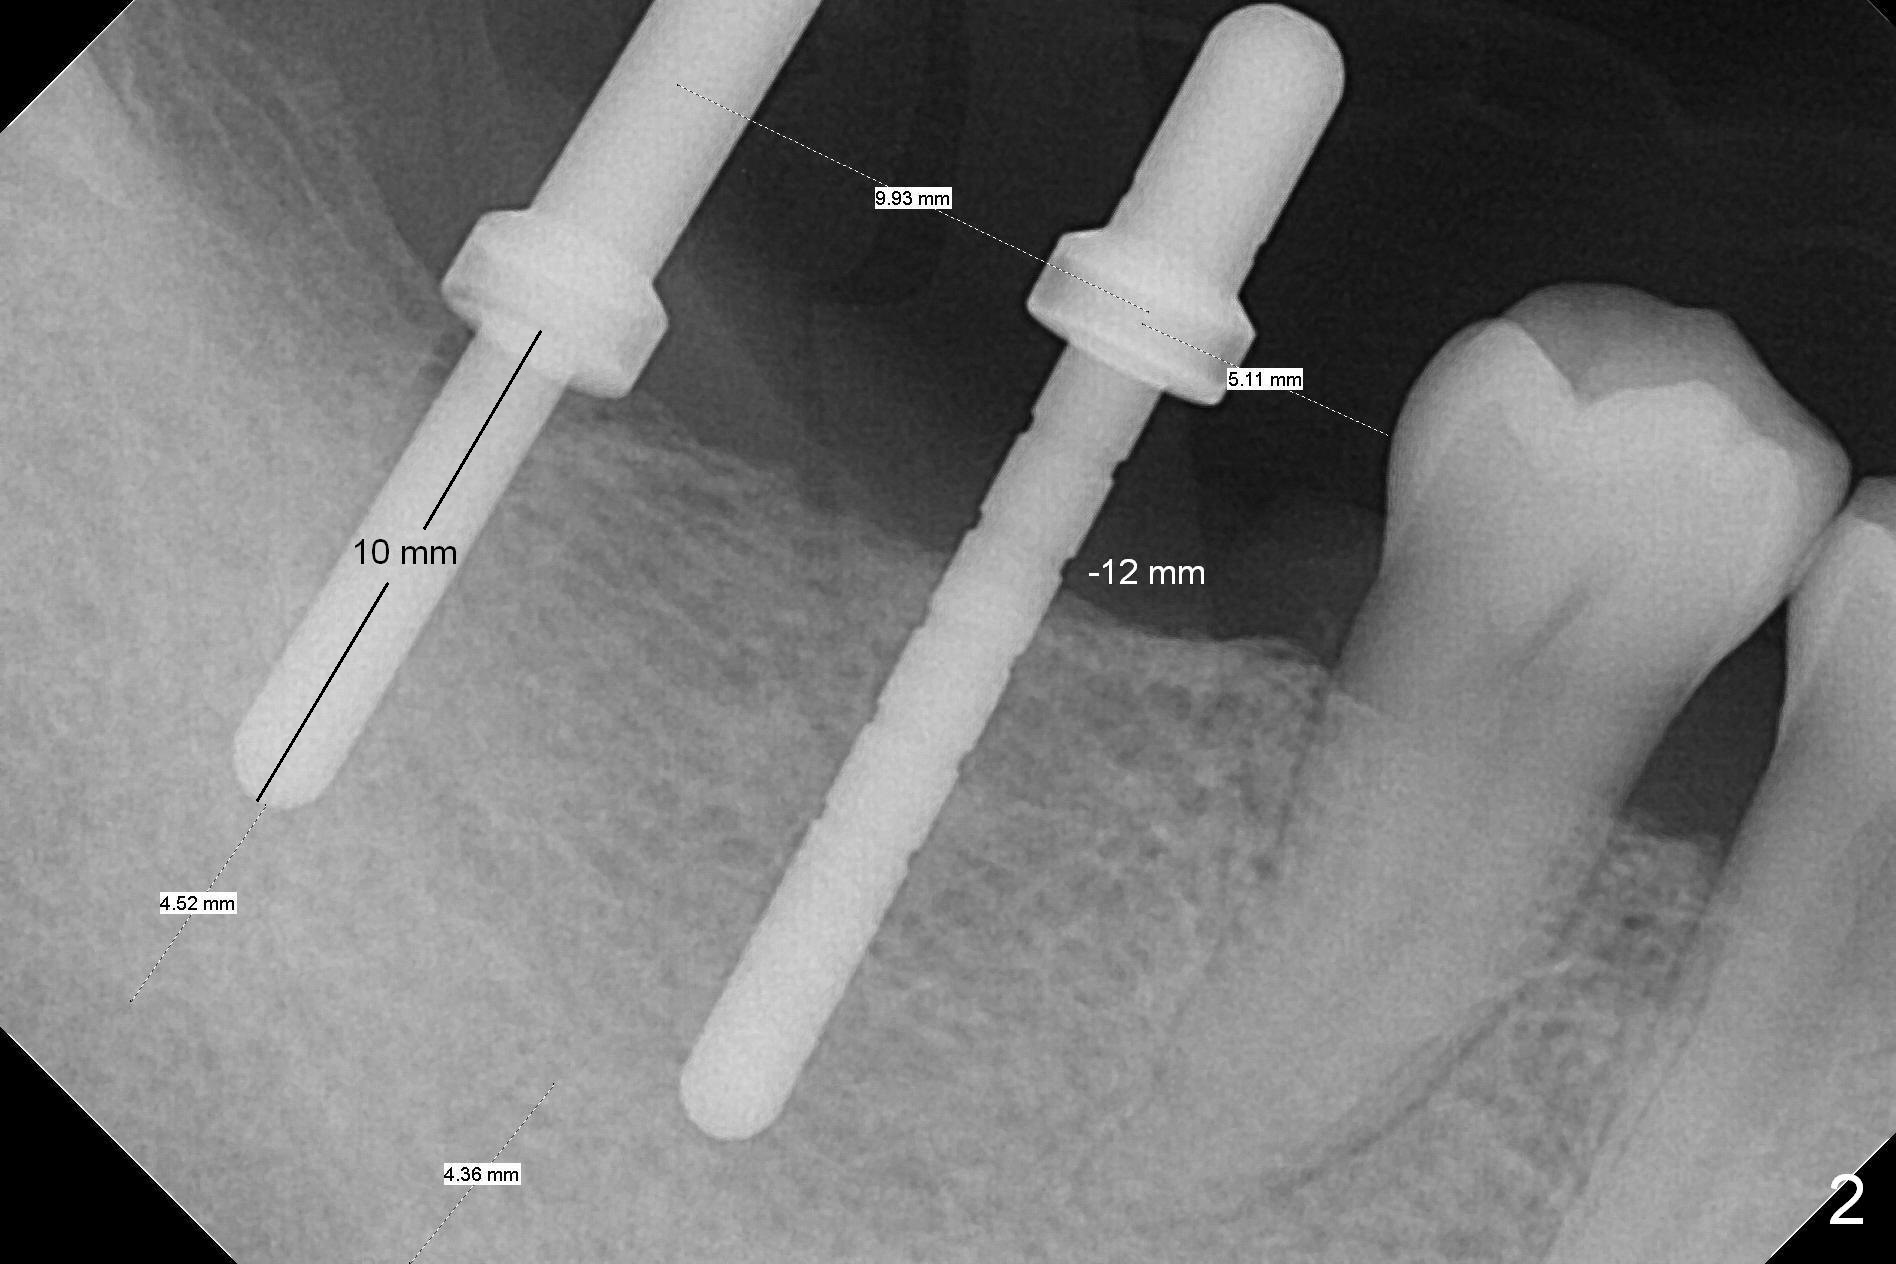

The supraerupted tooth #2 is adjusted using the lower right surgical stent. Osteotomies are initiated by using starter drill through surgical stent over the ridge (Fig.1) prior to incision. The initial depths are 10 and 12 mm at the sites of #31 and 30, respectively (Fig.2). The new sensor with the existing sensor holder cannot reach the deep portion of the lingual vestibule (Fig.2,3). Without the sensor holder, the #2 sensor with rounded corners has no problem showing the Inferior Alveolar Canal (Fig.4 red dashed line). The two implants (5x12 and 5x14 mm, Fig.5) are placed with >50 Ncm. Cemented abutments are immediately placed (6.8x4(2) and 6.8x4(3) mm) to reduce suture tension (after autogenous bone graft and collagen dressing) and hold periodontal dressing in place. The wound does not heal completely 15 days postop (Fig.6). The patient reveals that he smokes 1/2 pack per day. There is crestal bone resorption 4 months postop (Fig.7 *). It appears that for smokers, implants should be smaller, placed deeper and buried. In addition, his oral hygiene is not good.